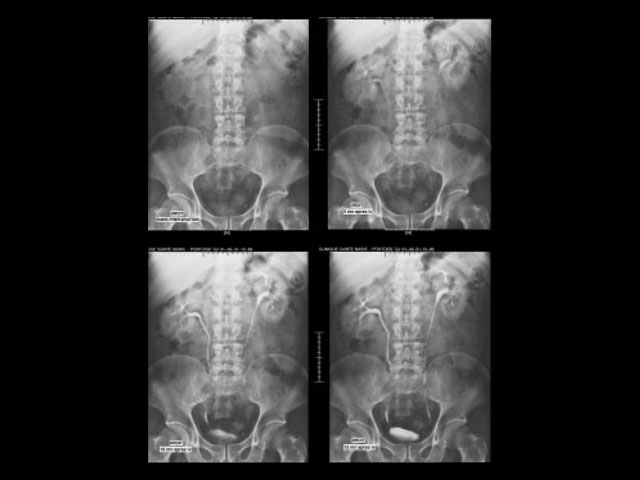

Επιπλέον ειδικές εξετάσεις όπως βαριούχο γεύμα και υποκλυσμός αλλά και ενδοφλέβια πυεολογραφία, διενεργούνται με ταχύτητα και ασφάλεια σε σύγχρονο και άνετο περιβάλλον.

Σημαντική είναι και η συνεισφορά στην παιδιατρική με τη διενέργεια ανιούσας κυστεοουρηθρογραφίας καθώς και στην γυναικολογία – μαιευτική με τη μέθοδο της σαλπιγγογραφίας.

Απεικόνιση 4